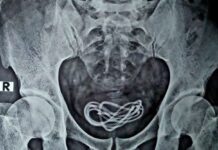

ജനനേന്ദ്രിയത്തിൽ ടാറ്റൂ ചെയ്ത 21 കാരനായ യുവാവിന് മൂന്നു മാസത്തോളം സ്ഥിരമായി ലിംഗോദ്ധാരണം ഉണ്ടായതായി റിപ്പോർട്ട്. പുരുഷലിംഗത്തെ ബാധിക്കുന്ന അപൂർവ്വ രോഗാവസ്ഥയായ പ്രിയാപിസമാണ് യുവാവിൽ ഉദ്ധാരണത്തിന് കാരണമായത്. ലൈംഗികോത്തേജനമില്ലാതെ, ദീർഘനേരത്തേക്ക് ലിംഗോദ്ധാരണമുണ്ടാകുന്ന അപൂർവ അവസ്ഥയാണിത്. ഹാൻഡ് ഹെൽഡ് സൂചി ഉപയോഗിച്ചുള്ള പരമ്പരാഗത ടാറ്റൂ രീതിയിലാണ് യുവാവ്ജനനേന്ദ്രിയത്തിൽ ടാറ്റൂ ചെയ്തത്. ലിംഗത്തിലേക്കുള്ള രക്തയോട്ടം പരിശോധിച്ചപ്പോൾ ടാറ്റൂ ചെയ്ത ഭാഗത്ത് സ്യൂഡോഅനൂറിസം കണ്ടെത്തി. ധമനിയുടെ ഭിത്തിയിലുണ്ടാകുന്ന ക്ഷതം മൂലം രക്തം ധമനിയുടെ പുറത്തേക്ക് ഒഴുകുകയും ചുറ്റുമുള്ള കോശങ്ങളിൽ കട്ടപിടിക്കുകയും ചെയ്യുന്ന അവസ്ഥയാണിത്. തുടർന്നുള്ള പരിശോധനയിൽ യുവാവിന് പ്രിയാപിസത്തിൻറെ വിഭാഗങ്ങളിൽ ഒന്നായ ‘നോൺ-ഇസ്കെമിക് പ്രിയാപിസം’ ഉണ്ടെന്ന് കണ്ടെത്തുകയായിരുന്നു. ലിംഗത്തിലേക്ക് രക്തം അമിതമായി പ്രവഹിക്കുന്നതാണ് ഇതിനു കാരണം. ഇറാൻ പൗരനായ യുവാവ് ഇതിനുമുൻപും ജനനേന്ദ്രിയത്തിൽ ടാറ്റൂ ചെയ്തിട്ടുണ്ടെന്നാണ് ലൈവ് സയൻസിൻറെ റിപ്പോർട്ടിൽ പറയുന്നത്.